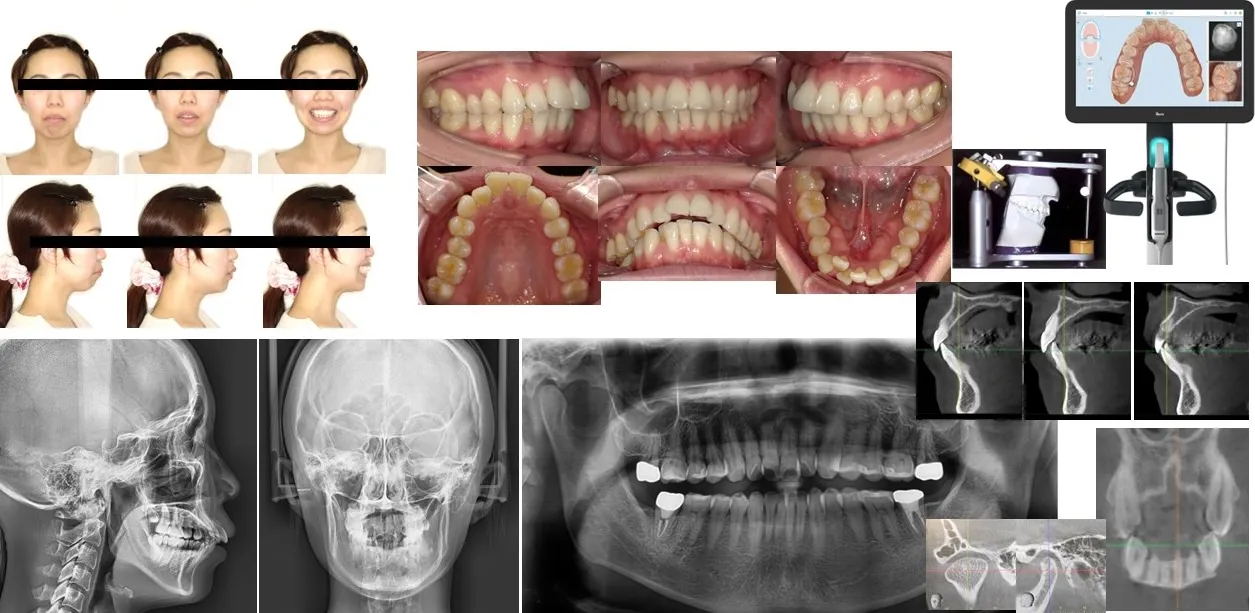

・診断学

資料採得/セファロ分析

矯正治療計画の立案

診断資料 ・クリンチェックの作成

・資料採得

顔貌・口腔内写真/レントゲン

スキャニング/咬合採得( CO・ CR)